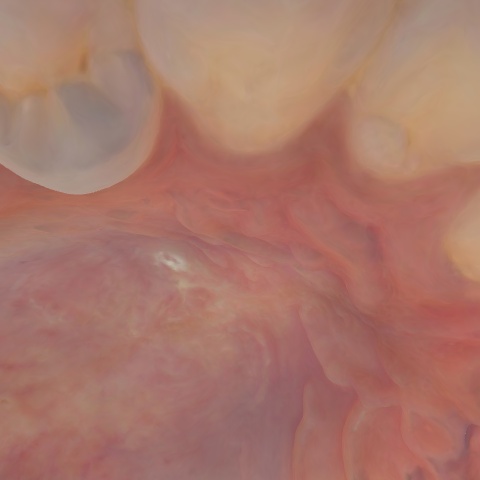

NHD29443

Overview

Annotated as "Good"